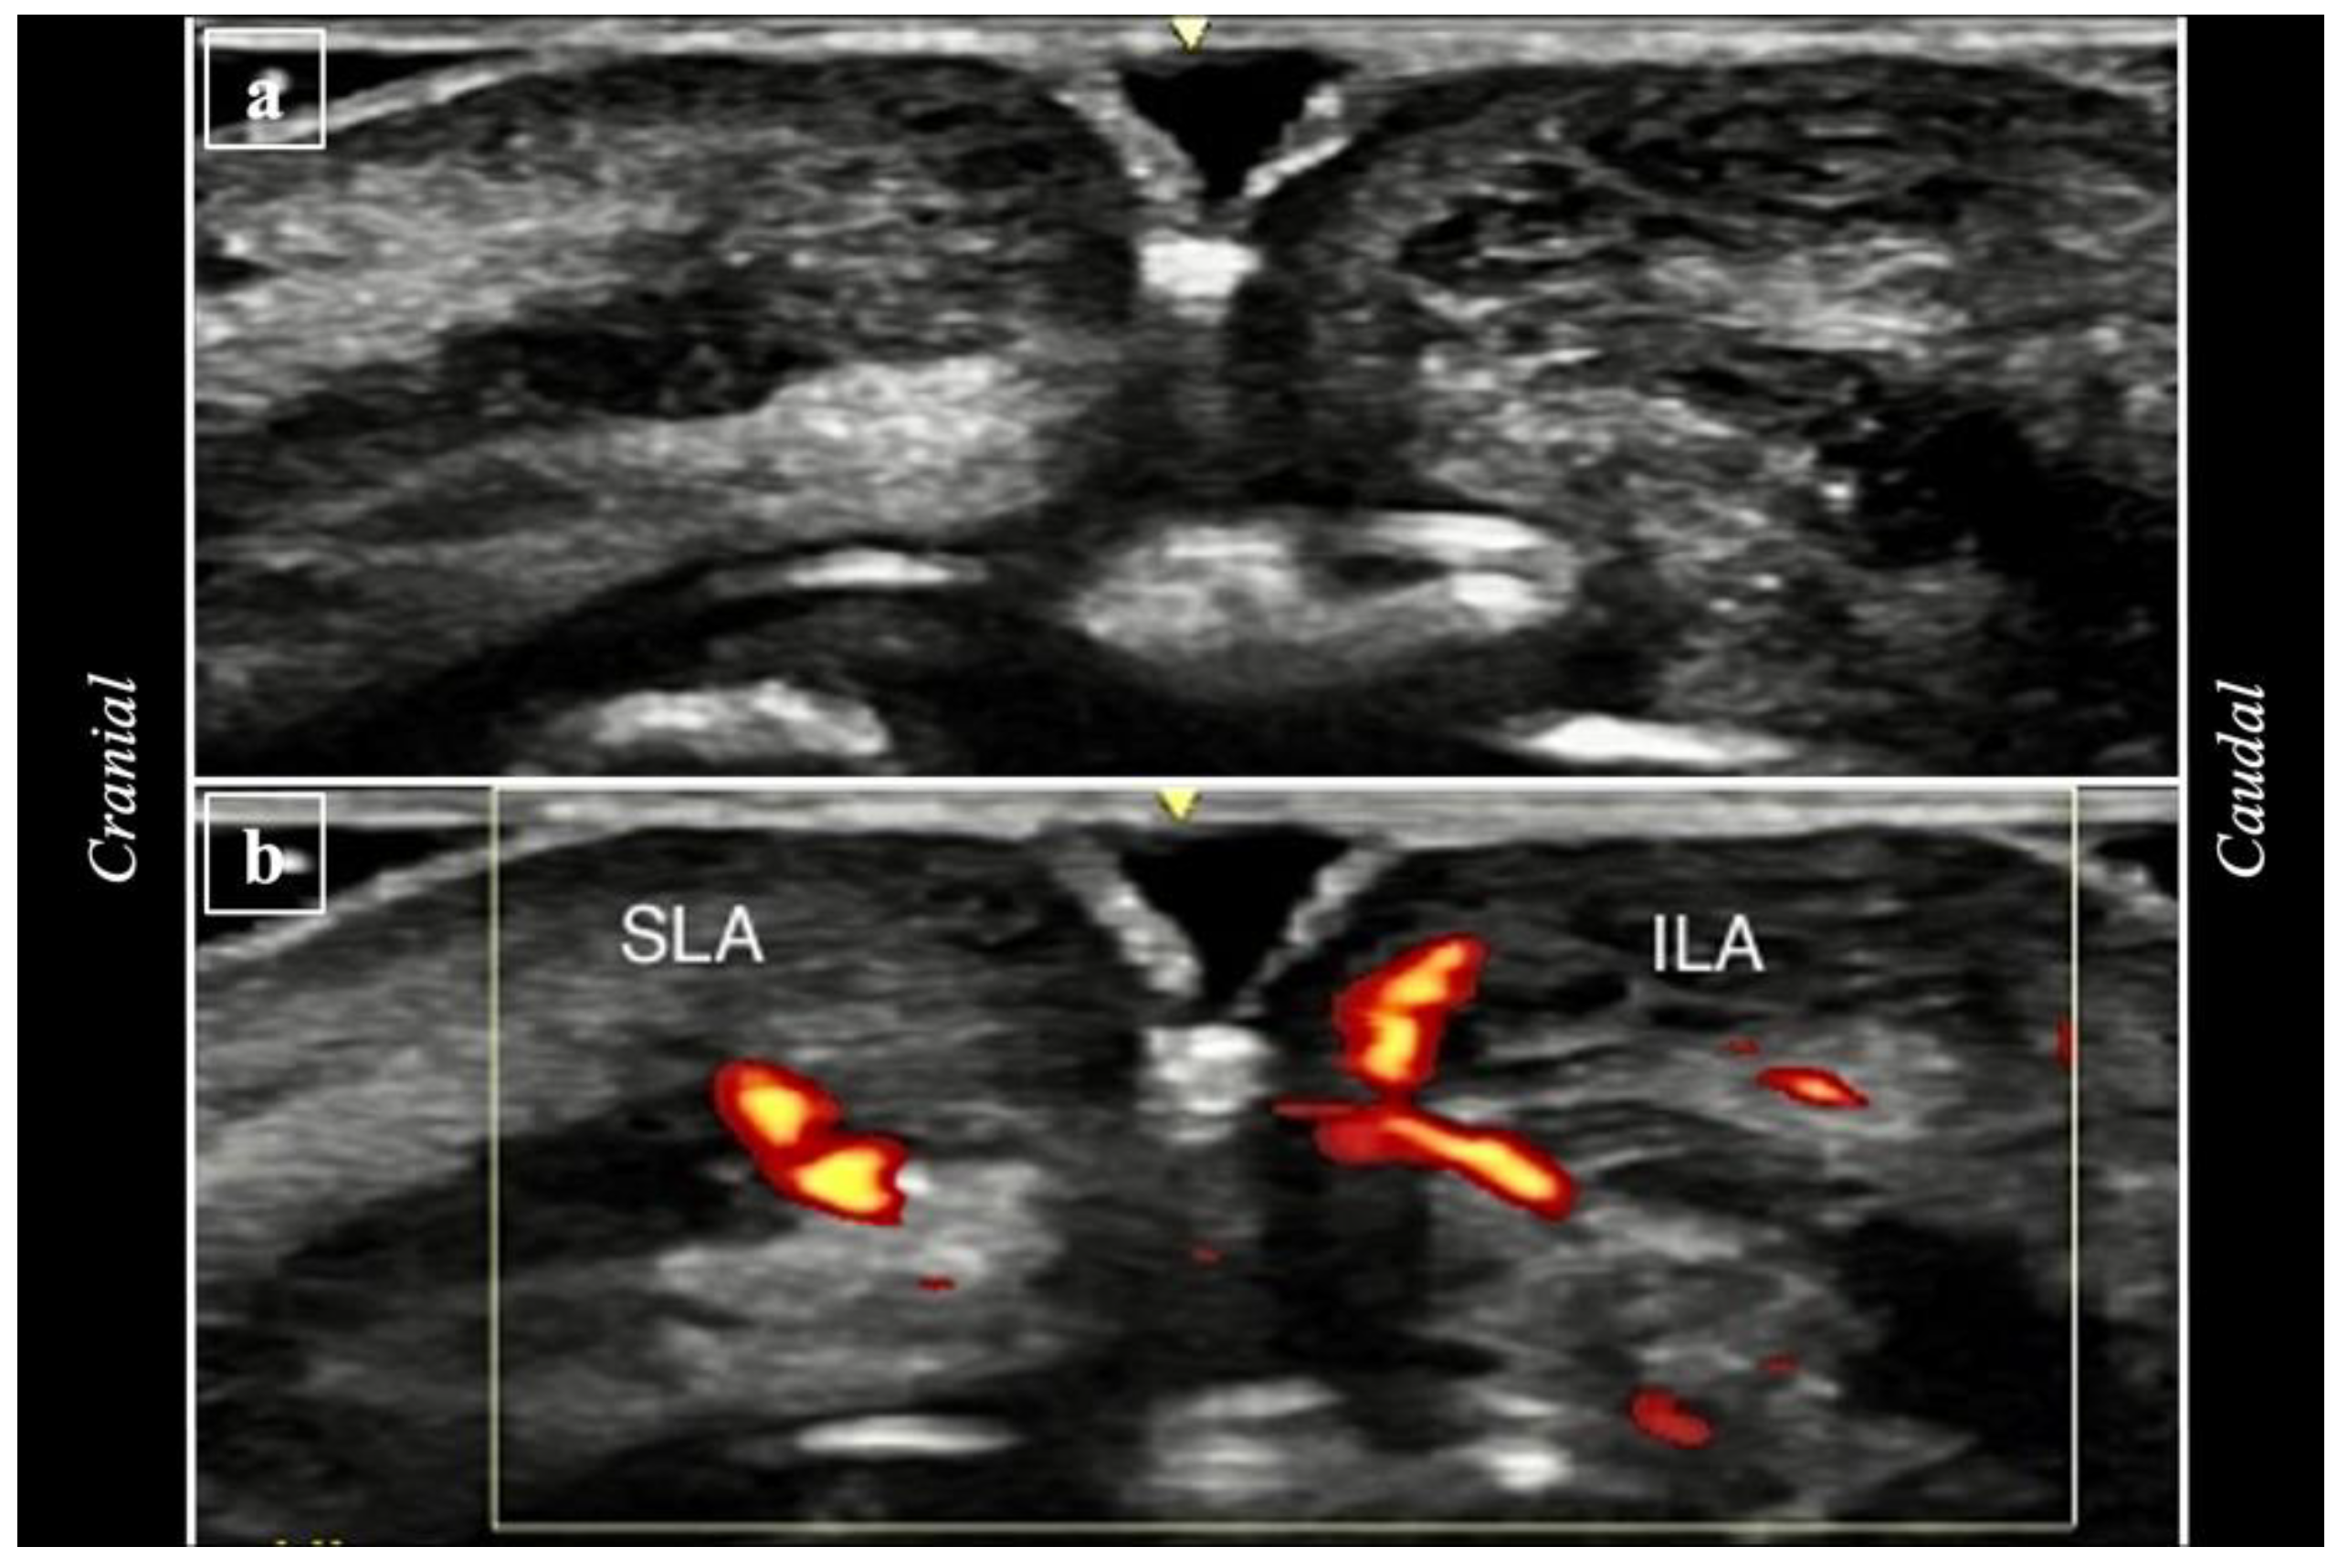

2.3. Ultrasound Analysis

- (i)

- (ii)

- Post-procedure imaging (T2) involved capturing new images in the same vertical positions in A1, A2, A3, A4, and A5 (Figure 7).